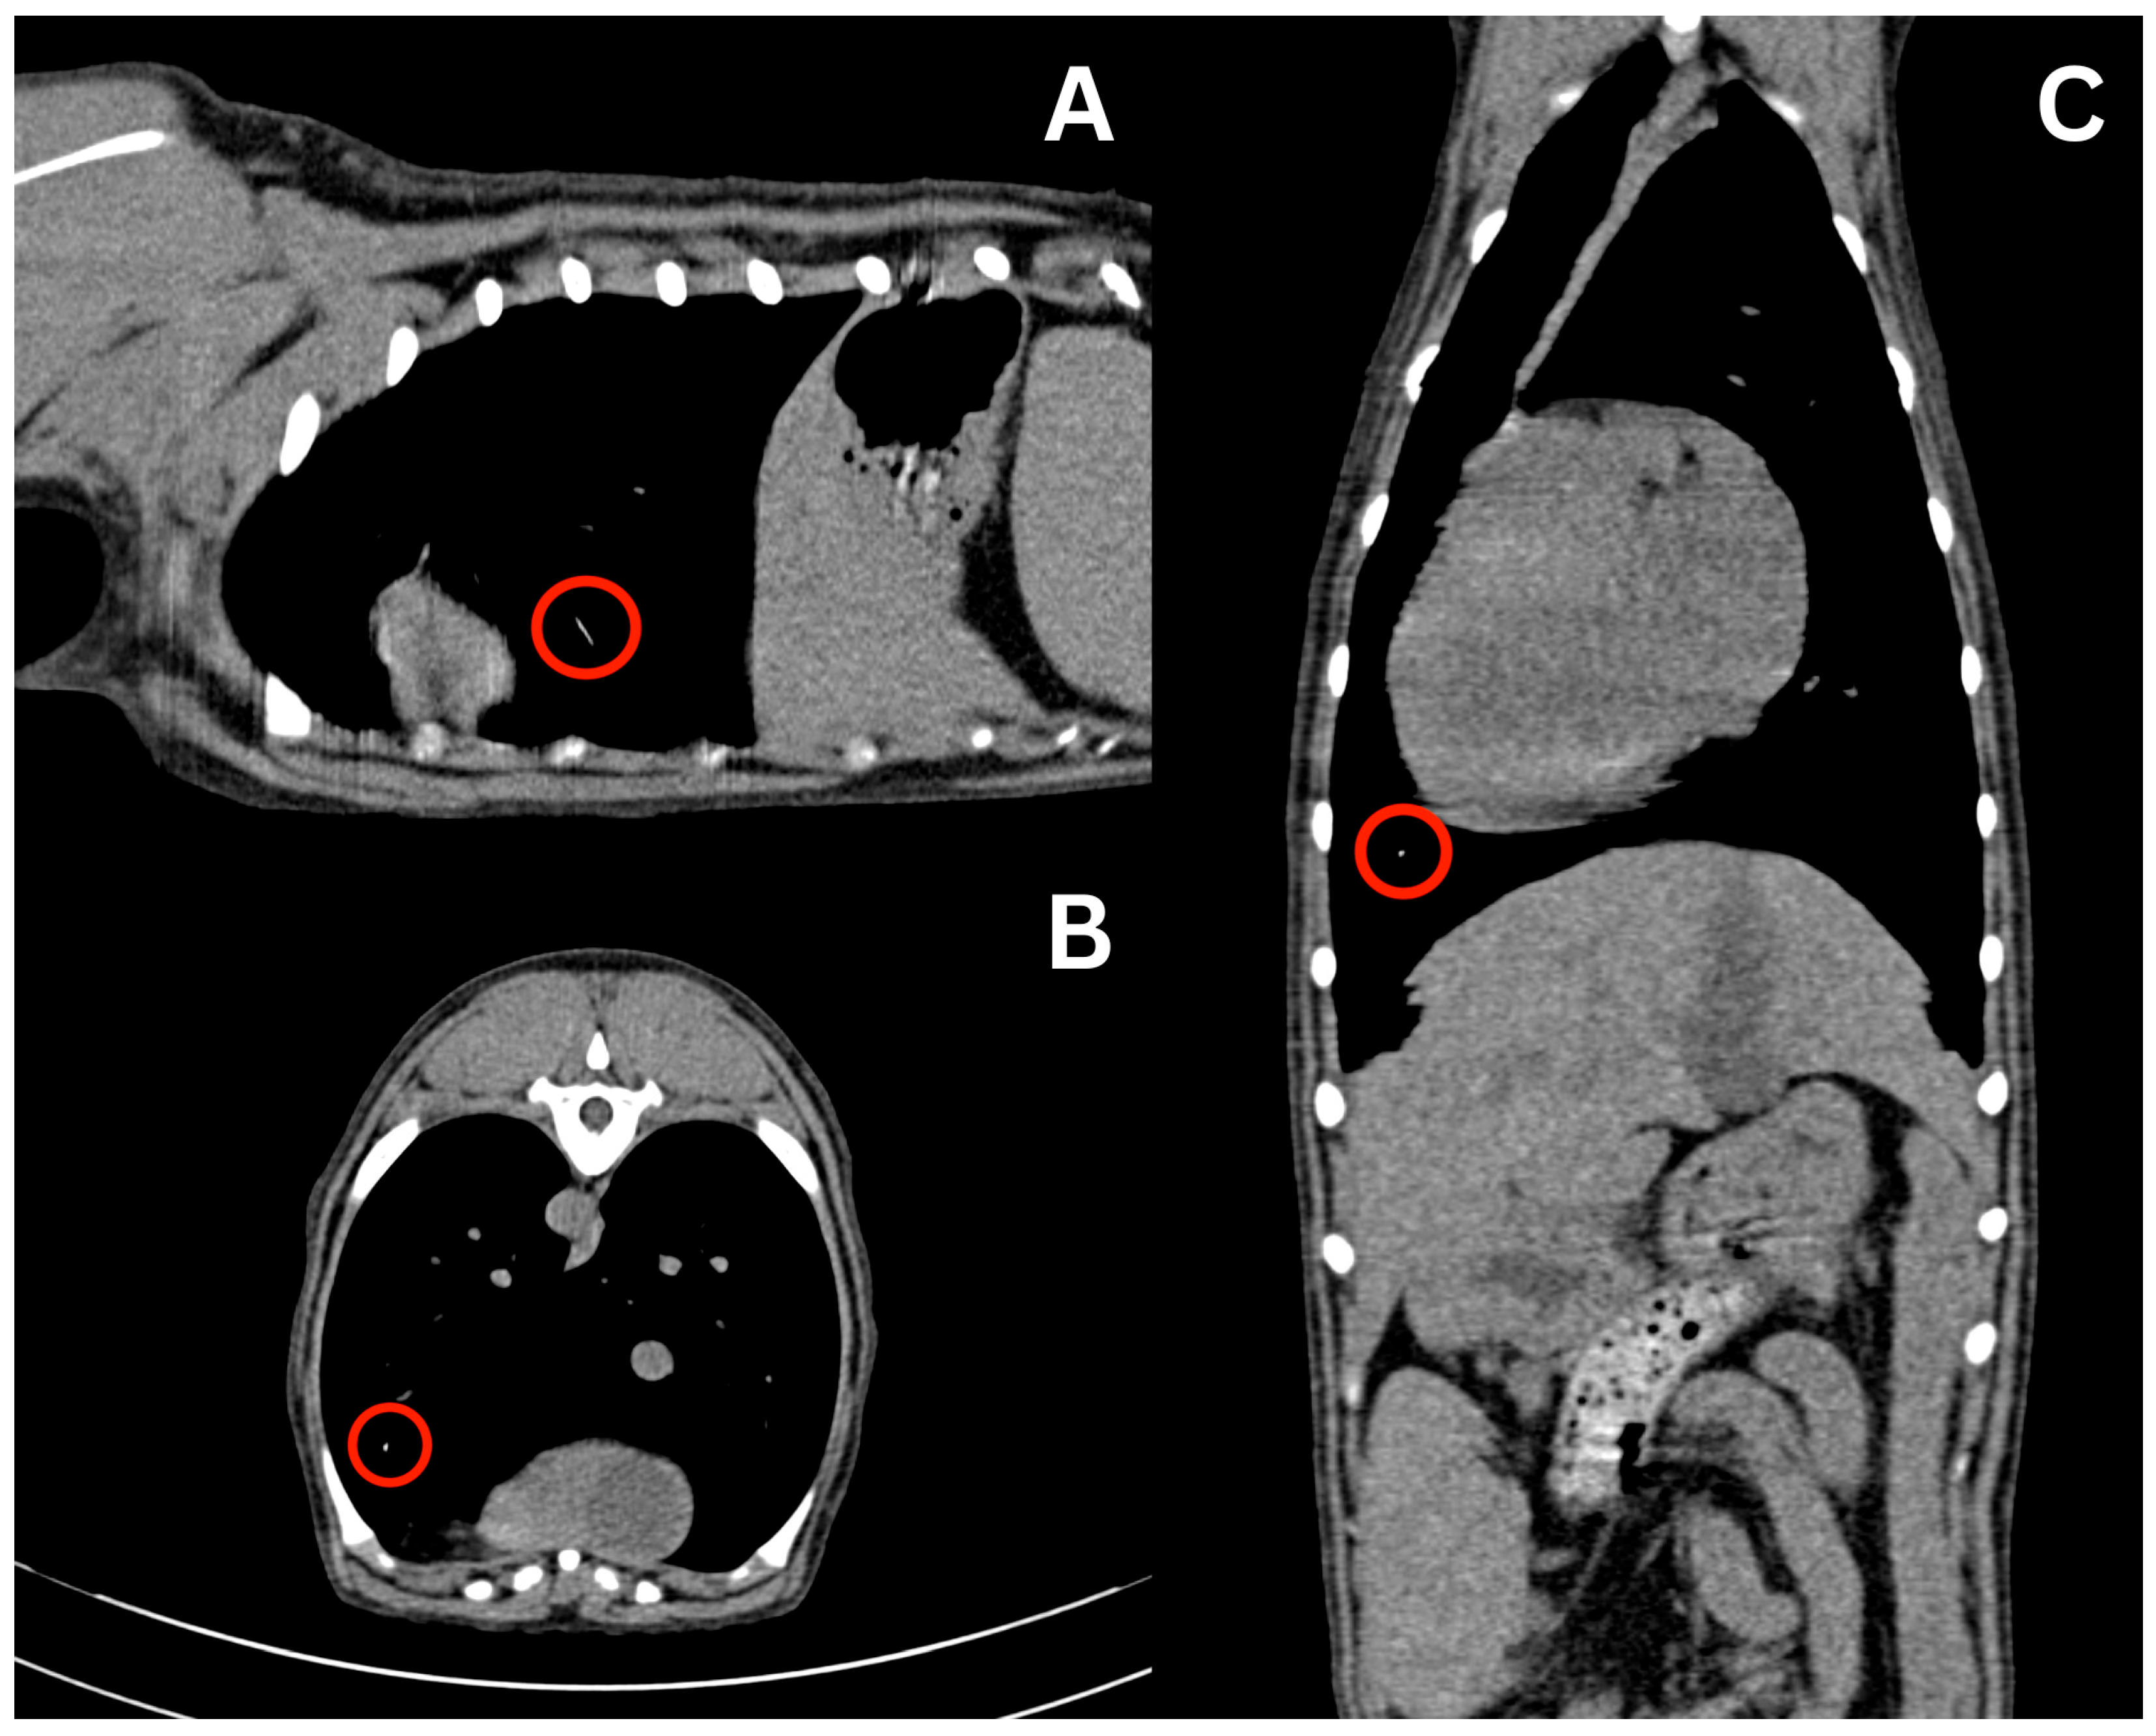

At the time of presentation to the emergency department, the patient had no clinical signs. Physical examination was unremarkable other than her missing 404 tooth with stitches in place and a shaved right cephalic region from the prior PIVC site. Remnants of the PIVC were compared to an actual 20-gauge PIVC. The estimated missing catheter tip was 18–22 mm long. At this point, a full-body CT scan was recommended, for which the patient was anesthetized on the same day. The patient was premedicated with 0.004 mg/kg of fentanyl (50 mcg/mL, Fentanyl Citrate, Hospira, Lake Forest, IL, USA) IV, and then induced with 0.2 mg/kg of midazolam (5 mg/mL, Midazolam Injection, Avet Pharmaceuticals, East Brunswick, NJ, USA) IV and propofol to with a total volume of 6 mL IV. Anesthesia was maintained with isoflurane in 100% oxygen. The patient was placed in sternal recumbency for the CT scan (Somatom Emotion 16, Siemens Healthineers, Malvern, PA, USA). Protocol parameters were as follows: kVp: 130; exposure time: 600; and slice thickness: 0.75 mm. Initially, the full-body CT scan was unremarkable, with no linear hyperattenuating structure visualized in the cephalic vasculature, pulmonary vasculature, or cardiac silhouette. The skull, cervical region, thorax, abdomen, pelvis, and pelvic limbs were reported as normal, and no remnant of the PIVC could initially be identified. No complications occurred during anesthesia and recovery post-operatively was uneventful. The patient was discharged the same day. Since the PIVC had to be present in the patient, a misdiagnosis was suspected. The authors requested a second opinion from another board-certified radiologist, and the CT report was amended as a small linear hyperattenuating structure was visualized in the ventral aspect of the left caudal lung lobe, as seen in Figure 2. It was assumed that this was the PIVC tip due to the difference in Hounsfield Units (HU) between the linear structure of the PIVC (60 to 100 HU) compared to the surrounding blood vessels (30 to 60 HU) and lung parenchyma. The surrounding pulmonary parenchyma was normal with no pulmonary thromboembolism.

Figure 2. CT scan displaying hyperattenuating linear structure in the left ventral lung lobe, suspected at the time to be the migrated intravenous catheter estimated to be 20 mm in length. Sagittal (A), axial (B), and coronal (C) views are displayed with visualization of the suspected structure in each view indicated by the red circle.

Due to these findings, the patient was readmitted the next day for a left lateral thoracotomy with potential lung lobectomy. A repeat CT scan was recommended to verify the location of the PIVC tip immediately prior to surgery. A complete blood count (CBC) and non-steroidal anti-inflammatory drug (NSAID) panel, consisting of alkaline phosphatase, alanine aminotransferase, aspartate aminotransferase, blood urea nitrogen, and creatinine performed prior to repeat CT imaging, showed no abnormalities except eosinopenia (0.00 K/uL; reference range: 0.06–1.23 K/uL). The initial partial thromboplastin time (PTT) result (>300.0 s with a reference range of 72–102 s) was considered erroneous; repeat testing confirmed a value within the reference range of 93.0 s. The patient underwent general anesthesia and was premedicated with 1 mg/kg of maropitant and 0.19 mg/kg of hydromorphone (10 mg/mL, Hydromorphone Hydrochloride, Pfizer, New York, NY, USA) IV. She was then induced with 0.2 mg/kg of midazolam IV and propofol to affect with a total of 6 mL IV (3.2 mg/kg total). She was maintained on isoflurane in 100% oxygen with IV crystalloid fluids at 5 mL/kg/h. CT verified that the linear hyperattenuating structure remained in the peripheral pulmonary artery within the ventral aspect of the left caudal lung lobe.